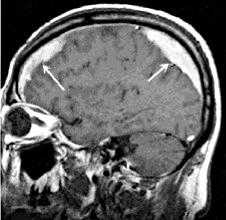

(а) Бесконтрастная КТ: у пожилого пациента с множественными падениями в анамнезе определяется разделенное на полости скопление «пенящейся» жидкости. Отмечаются многочисленные границы раздела кровь - жидкость.

(б) КТ-ангиография: у этого же пациента определяется скопление «пенящейся» жидкости в форме полумесяца. Обратите внимание на смещение кнутри головного мозга, а также компрессию борозд и смещение корковых вен.